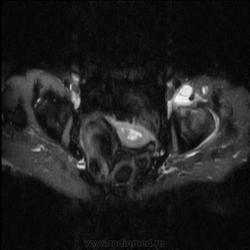

МРТ тазобедренный сустав (срочно)

Пациентка 1944г. р. Жалобы на боль области сустава в течении месяца. Температуры не отмечала. Серьезных травм со слов не было. Внешний осмотр новых данных не дал.

Дайкомы пока не смотрела-скорость интернета дома небольшая.Думаю, что здесь проблемы в суставе и параартикулярных мягких тканях.Не так давно у меня что-то похожее было.

типа бурсита тазобедренного сустава? подвздошно-гребешковая сумка получается

А как вам стенка прямой кишки?

Подозрительная, но неубедительно пока.Ни одного сагитталла не вижу с прямой кишкой.Нужно дообследовать однозначно.